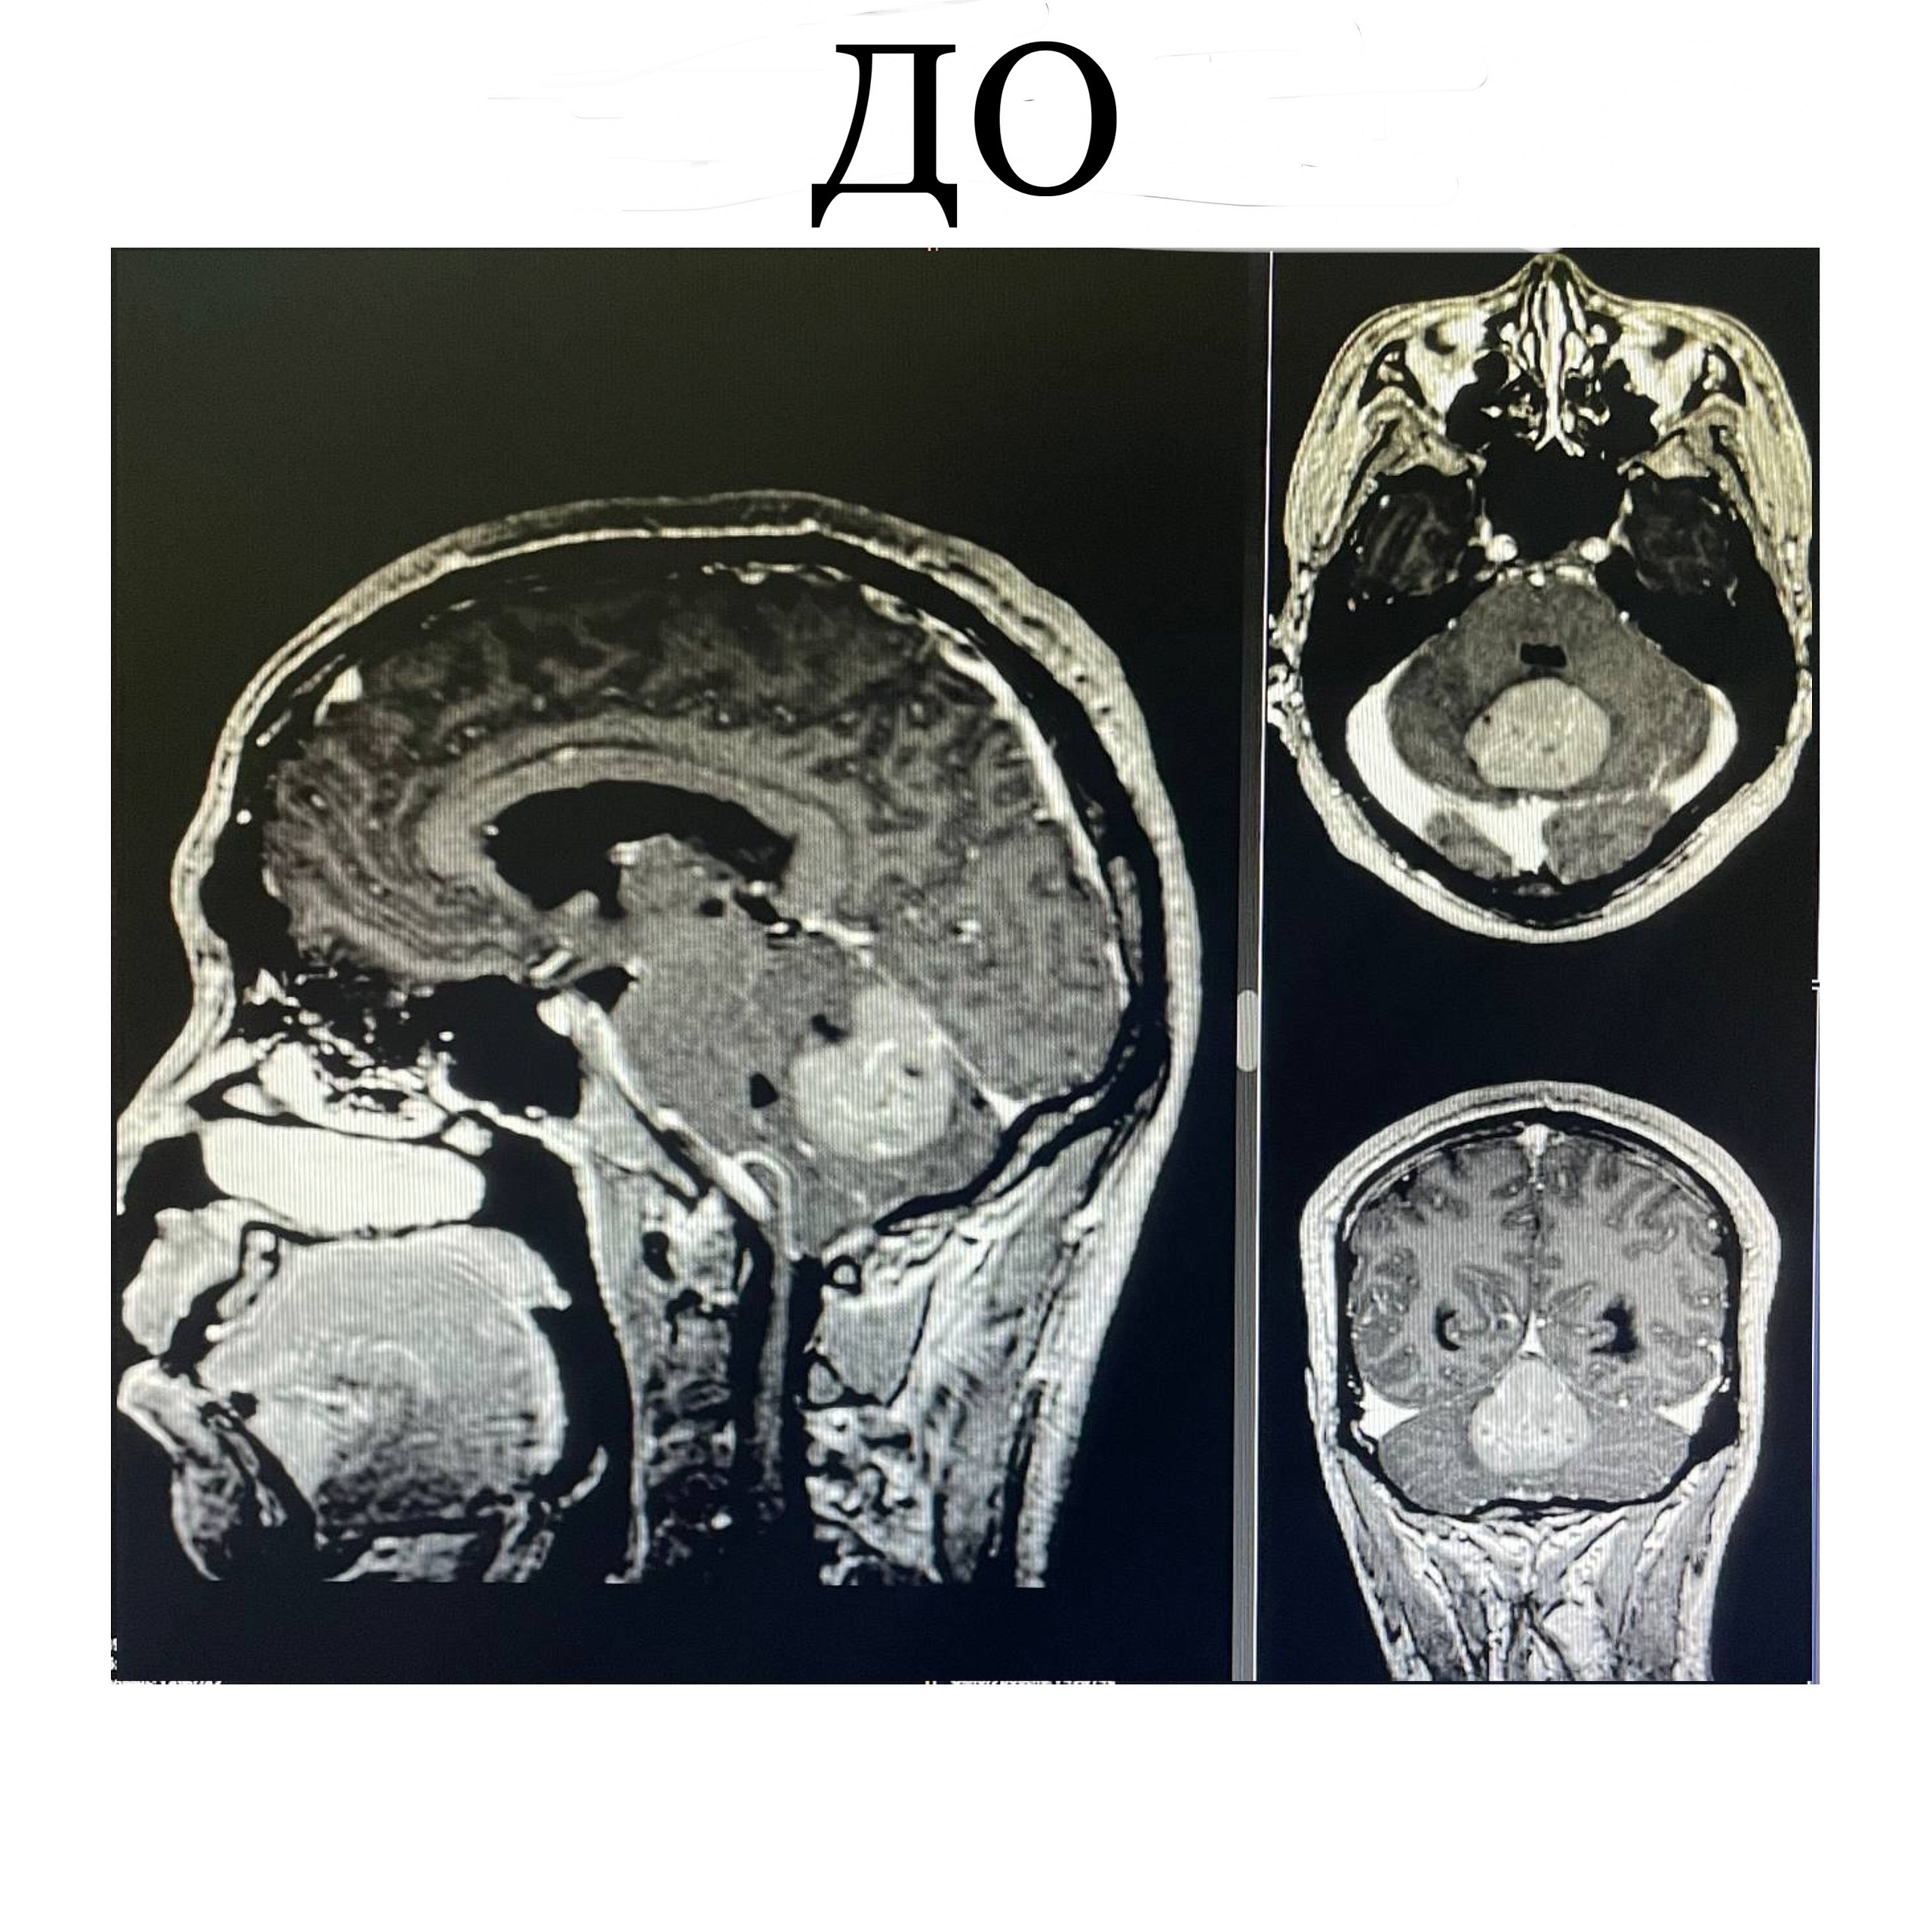

6 марта экстренно мужчина поступает в приемный покой РКБ им. Н.А. Семашко. Причина ухудшения была установлена довольно быстро - опухоль размером с мячик для пинг-понга (!). Она росла в затылочной области, а именно в мозжечке:

«Опухоли мозжечка составляют примерно 30% от всех опухолей головного мозга. Единственным методом лечения при таком большом размере является хирургическое вмешательство. Дело в том, что образование вызывает сдавливание ствола головного мозга, который фактически отвечает за всю жизнедеятельность нашего организма», - отметил Василий Хунданов, заведующий нейрохирургическим отделением Республиканской больницы.